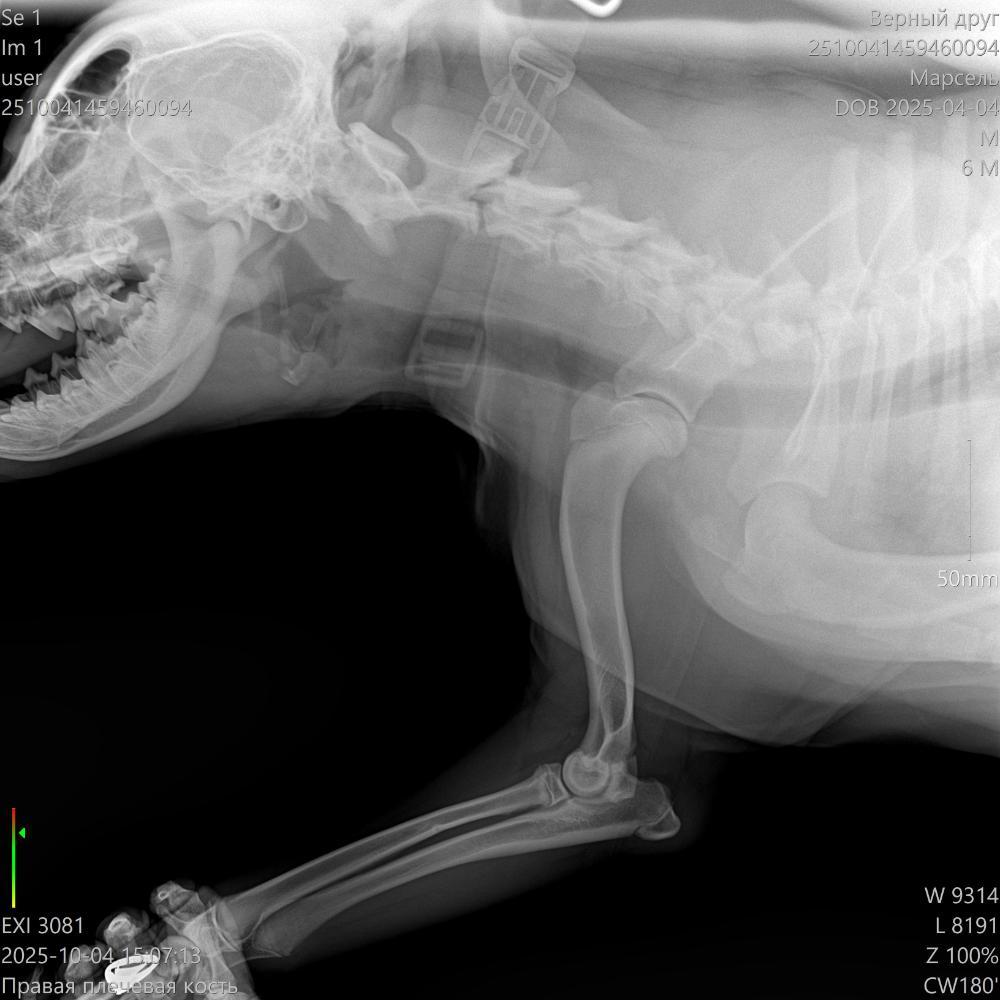

Здравствуйте. Щенок 6,5 месяцев начал периодически хромать на правую лапу. Сначала думали, что может ушиб или потянул лапу, съездили в клинику, нас отправили к ортопеду. Сходили к нему и сделали ренген и КТ. По результатам КТ: "Заключение: 1. Признаки РОХа (расслаивающий остеохондрит) в структуре медиальных надмыщелков плечевых костей обоих локтевых суставов (в правом локтевом суставе выражено в большей степени)."

После КТ были у 2 ортопедов. Один говорит, что нужно срочно делать операцию, второй выписал таблетки и сказал понаблюдать пару месяцев. Подскажите, пожалуйста, может кто-то сталкивался с таким заболеванием? Что лучше - подождать и понаблюдать или делать операцию? Если ждать, то не упустим ли время, а если делать операцию, то щенок еще растет, как это скажется на растущем организме?

2510041459460094_Марсель__04-10-2025 15_12_01_1-3.jpg